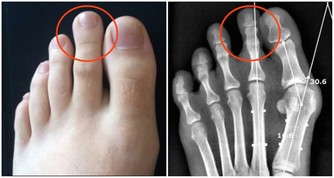

2. 預防骨質疏鬆的鈣片。

很多人秉持「吃什麼補什麼」的觀念,服用大量的鈣片來增加骨骼密度、預防骨質疏鬆,但其實目前鈣片還沒被證實有實質的效用,而且攝取過多也可能對心臟血管造成負擔。不過,因為鈣片內含維他命D,可以幫助人體吸收鈣質,所以對某些人來說還是多少有效。但如果你只是要補充鈣質的話,只要在日常飲食中,攝取一些優格或起司就足夠了。